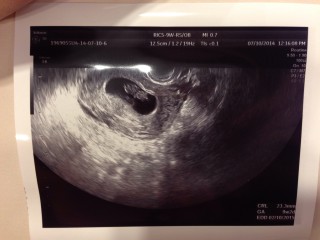

9w2d。 初めての妊娠(*^^*) 新婚旅行の2日前にわかりました❗(笑) もう可愛くて可愛くて仕方ないです(^o^)🍀 次の検診待ち遠しいo(^o^)o

2週間前に8wぐらいの大きさだと言われたのですが、本日9w2dで出産予定日確定しました☆心当たりのある日から自分で計算した週数とも合ってました(´ω`)次回は3週間後です!

特につわりがなくて検診までは無事に育ってくれているのか不安でいっぱいでしたが、ちゃんと二頭身に成長してくれていて安心しました! 大きさは22.9mmで先生にも標準サイズで元気に育ってますねと言われて嬉しかったです☆